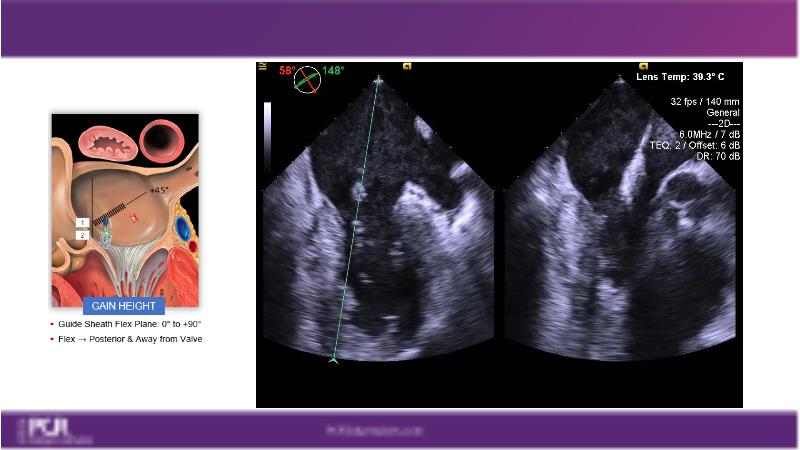

Watch this session to get an overview of a new TEER device, follow the step-by-step procedure related to initial experiences with this device for a Japanese patient with degenerative mitral regurgitation, learn about the latest data from RCT and registries, and follow discussions of challenging TEER cases!

- To learn procedural step-by-step of novel device